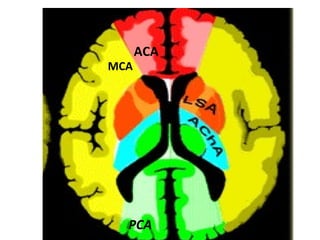

Cerebral Arterial Territory MCA -most of  lateral hemisphere ,  Basal ganglia, insula,  ACA- Inferomedial basal ganglia,ventromedial frontal lobes,  anterior 2/3rd medial cerebral hemispheres , 1 cm supero medial brain convexity PCA -Thalami, midbrain,  posterior 1/3of medial hemisphere , occipital lobe,  postero medial temporal lobe

Anterior Choroidal artery branch of  ICA  supply  part of the hippocampus, the posterior limb of the internal capsule  Medial lenticulostriate arteries Branches of the A1-segment of the  anterior cerebral artery.  They supply the  anterior inferior parts of the basal nuclei  and the  anterior limb of the internal capsule . Lateral lenticulostriate arteries Branches of the horizontal M1-segment of the  middle cerebral artery .  They supply the superior part of the  head  and the  body  of the  caudate nucleus ,  lentiform nucleus  and the  posterior limb of the internal capsule

MCA ACA PCA

Cerebral Arterial TerritoryMCA -most of lateral hemisphere , Basal ganglia, insula, ACA- Inferomedial basal ganglia,ventromedial frontal lobes, anterior 2/3rd medial cerebral hemispheres , 1 cm supero medial brain convexity PCA -Thalami, midbrain, posterior 1/3of medial hemisphere , occipital lobe, postero medial temporal lobe

Anterior Choroidal arterybranch of ICA supply part of the hippocampus, the posterior limb of the internal capsule Medial lenticulostriate arteries Branches of the A1-segment of the anterior cerebral artery. They supply the anterior inferior parts of the basal nuclei and the anterior limb of the internal capsule . Lateral lenticulostriate arteries Branches of the horizontal M1-segment of the middle cerebral artery . They supply the superior part of the head and the body of the caudate nucleus , lentiform nucleus and the posterior limb of the internal capsule